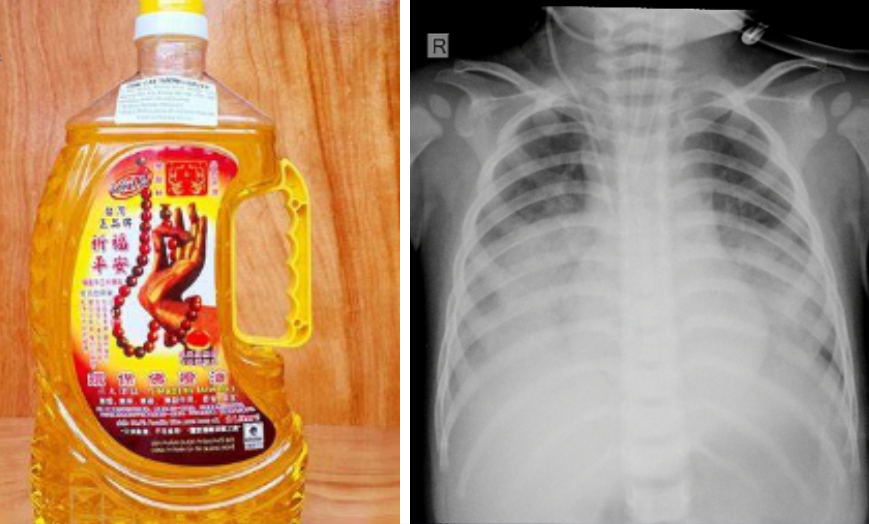

| Loại dầu thắp đèn cháu bé uống dẫn đến bị ngộ độc, viêm phổi nặng và trong tình trạng nguy kịch. |

Nhập viện trong tình trạng suy hô hấp, da tái, viêm phổi nặng, cháu bé lập tức được các bác sĩ hỗ trợ hô hấp bằng thở máy áp lực cao đồng thời dùng kháng sinh phổ rộng. Sau khi cấp cứu, bệnh nhi vẫn đang trong tình trạng nguy kịch và được các bác sĩ theo dõi sát sao.